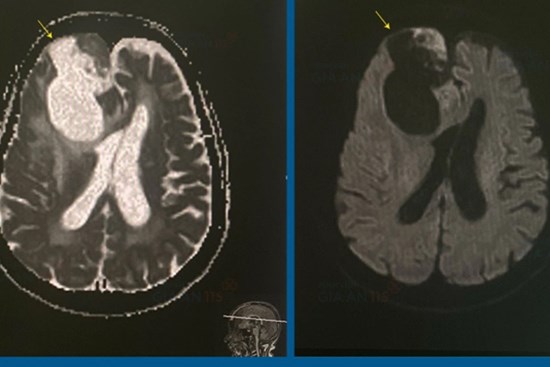

4 giờ cân não để phẫu thuật khối u não khổng lồ cho cụ bà 83 tuổi

Bệnh viện Gia An 115 (quận Bình Tân, TP.HCM) vừa phẫu thuật thành công lấy khối u não khổng lồ cho cụ bà 83 tuổi.